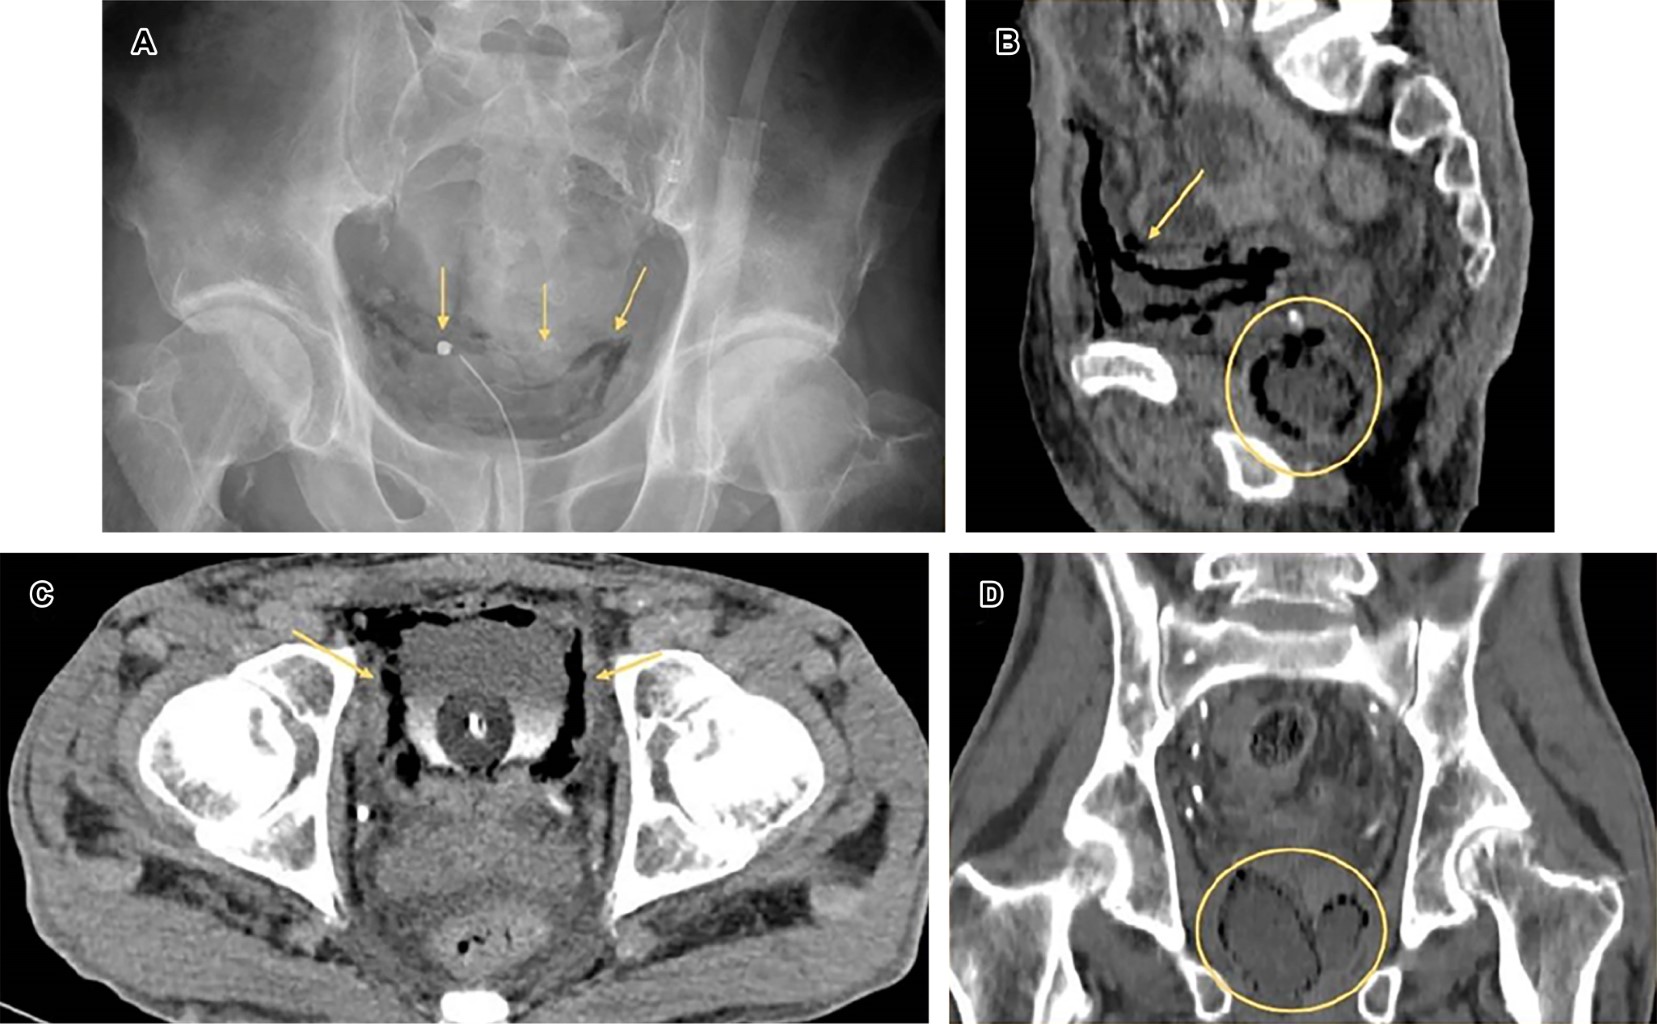

Emphysematous cystoprostatitis, radiological findings of an unusual entity

Introduction: emphysematous cystoprostatitis is a rare disease characterized by the accumulation of gas and purulent exudates in the prostate gland and bladder. Clinical case: 63-year-old man with poor general condition with symptoms of sepsis and abdominal pain. Radiological tests reveal the presence of gas in the bladder and prostate, as well as kidney damage. Conclusion: it is important to know the radiographic signs to obtain an early diagnosis and plan appropriate treatment.

Figure 1